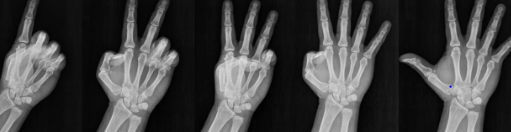

1. 손가락 스트레칭: 손바닥을 펴고 손가락을 최대한 벌린 후, 천천히 원래 위치로 돌아오게 합니다. 이 동작을 10회 반복합니다.

2. 손가락 굽히기: 손가락 끝을 손바닥 쪽으로 천천히 굽혔다가 펴는 운동을 합니다. 각 손가락마다 10회씩 반복합니다.

3. 손목 회전: 팔을 앞으로 뻗고 손목을 천천히 회전시킵니다. 시계 방향과 반시계 방향으로 각각 10회씩 반복합니다.

4. 손가락 저항 운동: 엄지와 다른 손가락을 하나씩 맞대고 약간의 저항을 주면서 누르고, 이 상태를 몇 초간 유지합니다. 각 손가락마다 5회씩 반복합니다.

이러한 운동들은 손가락과 손목의 유연성을 높이고, 관절의 통증을 줄이며, 손의 힘을 강화하는 데 도움이 됩니다. 하지만 운동 전후에는 충분한 스트레칭을 해주는 것이 중요하며, 통증이 있을 경우에는 전문가와 상담하는 것이 좋습니다. 꾸준히 운동을 하여 건강한 손가락 관절을 유지해 보세요.